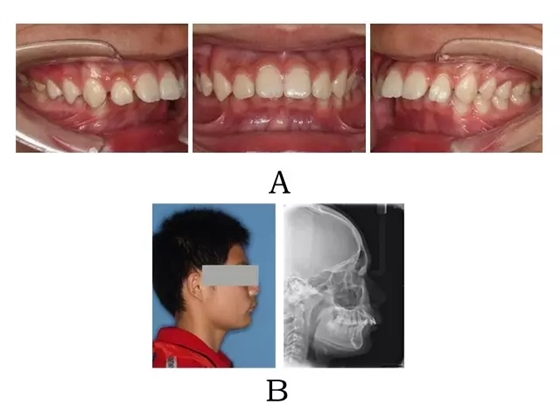

面型前突,面下部高度不足,頦唇溝較深??趦?nèi)表現(xiàn)為上頜骨源性前突,上前牙代償性直立或輕度唇傾;下頜后退伴深覆合深覆蓋,磨牙系遠(yuǎn)中關(guān)系。頭顱側(cè)位片下頜骨體部呈“長方形”,頦部形態(tài)較好(圖4-1)。

640.webp (1).jpg

圖4-1:混合I型突面畸形臨床表現(xiàn)及頭顱側(cè)位影像特征。

(A)齒槽與牙列特點(diǎn) (B)側(cè)貌與影像對比

Figure 4-1. Clinical manifestation and cephalometric image for merged skeletal and mandibular positional prognathism (Type I). (A) Alveolar and dentition specifics. (B) Facial profile and radiographic image.